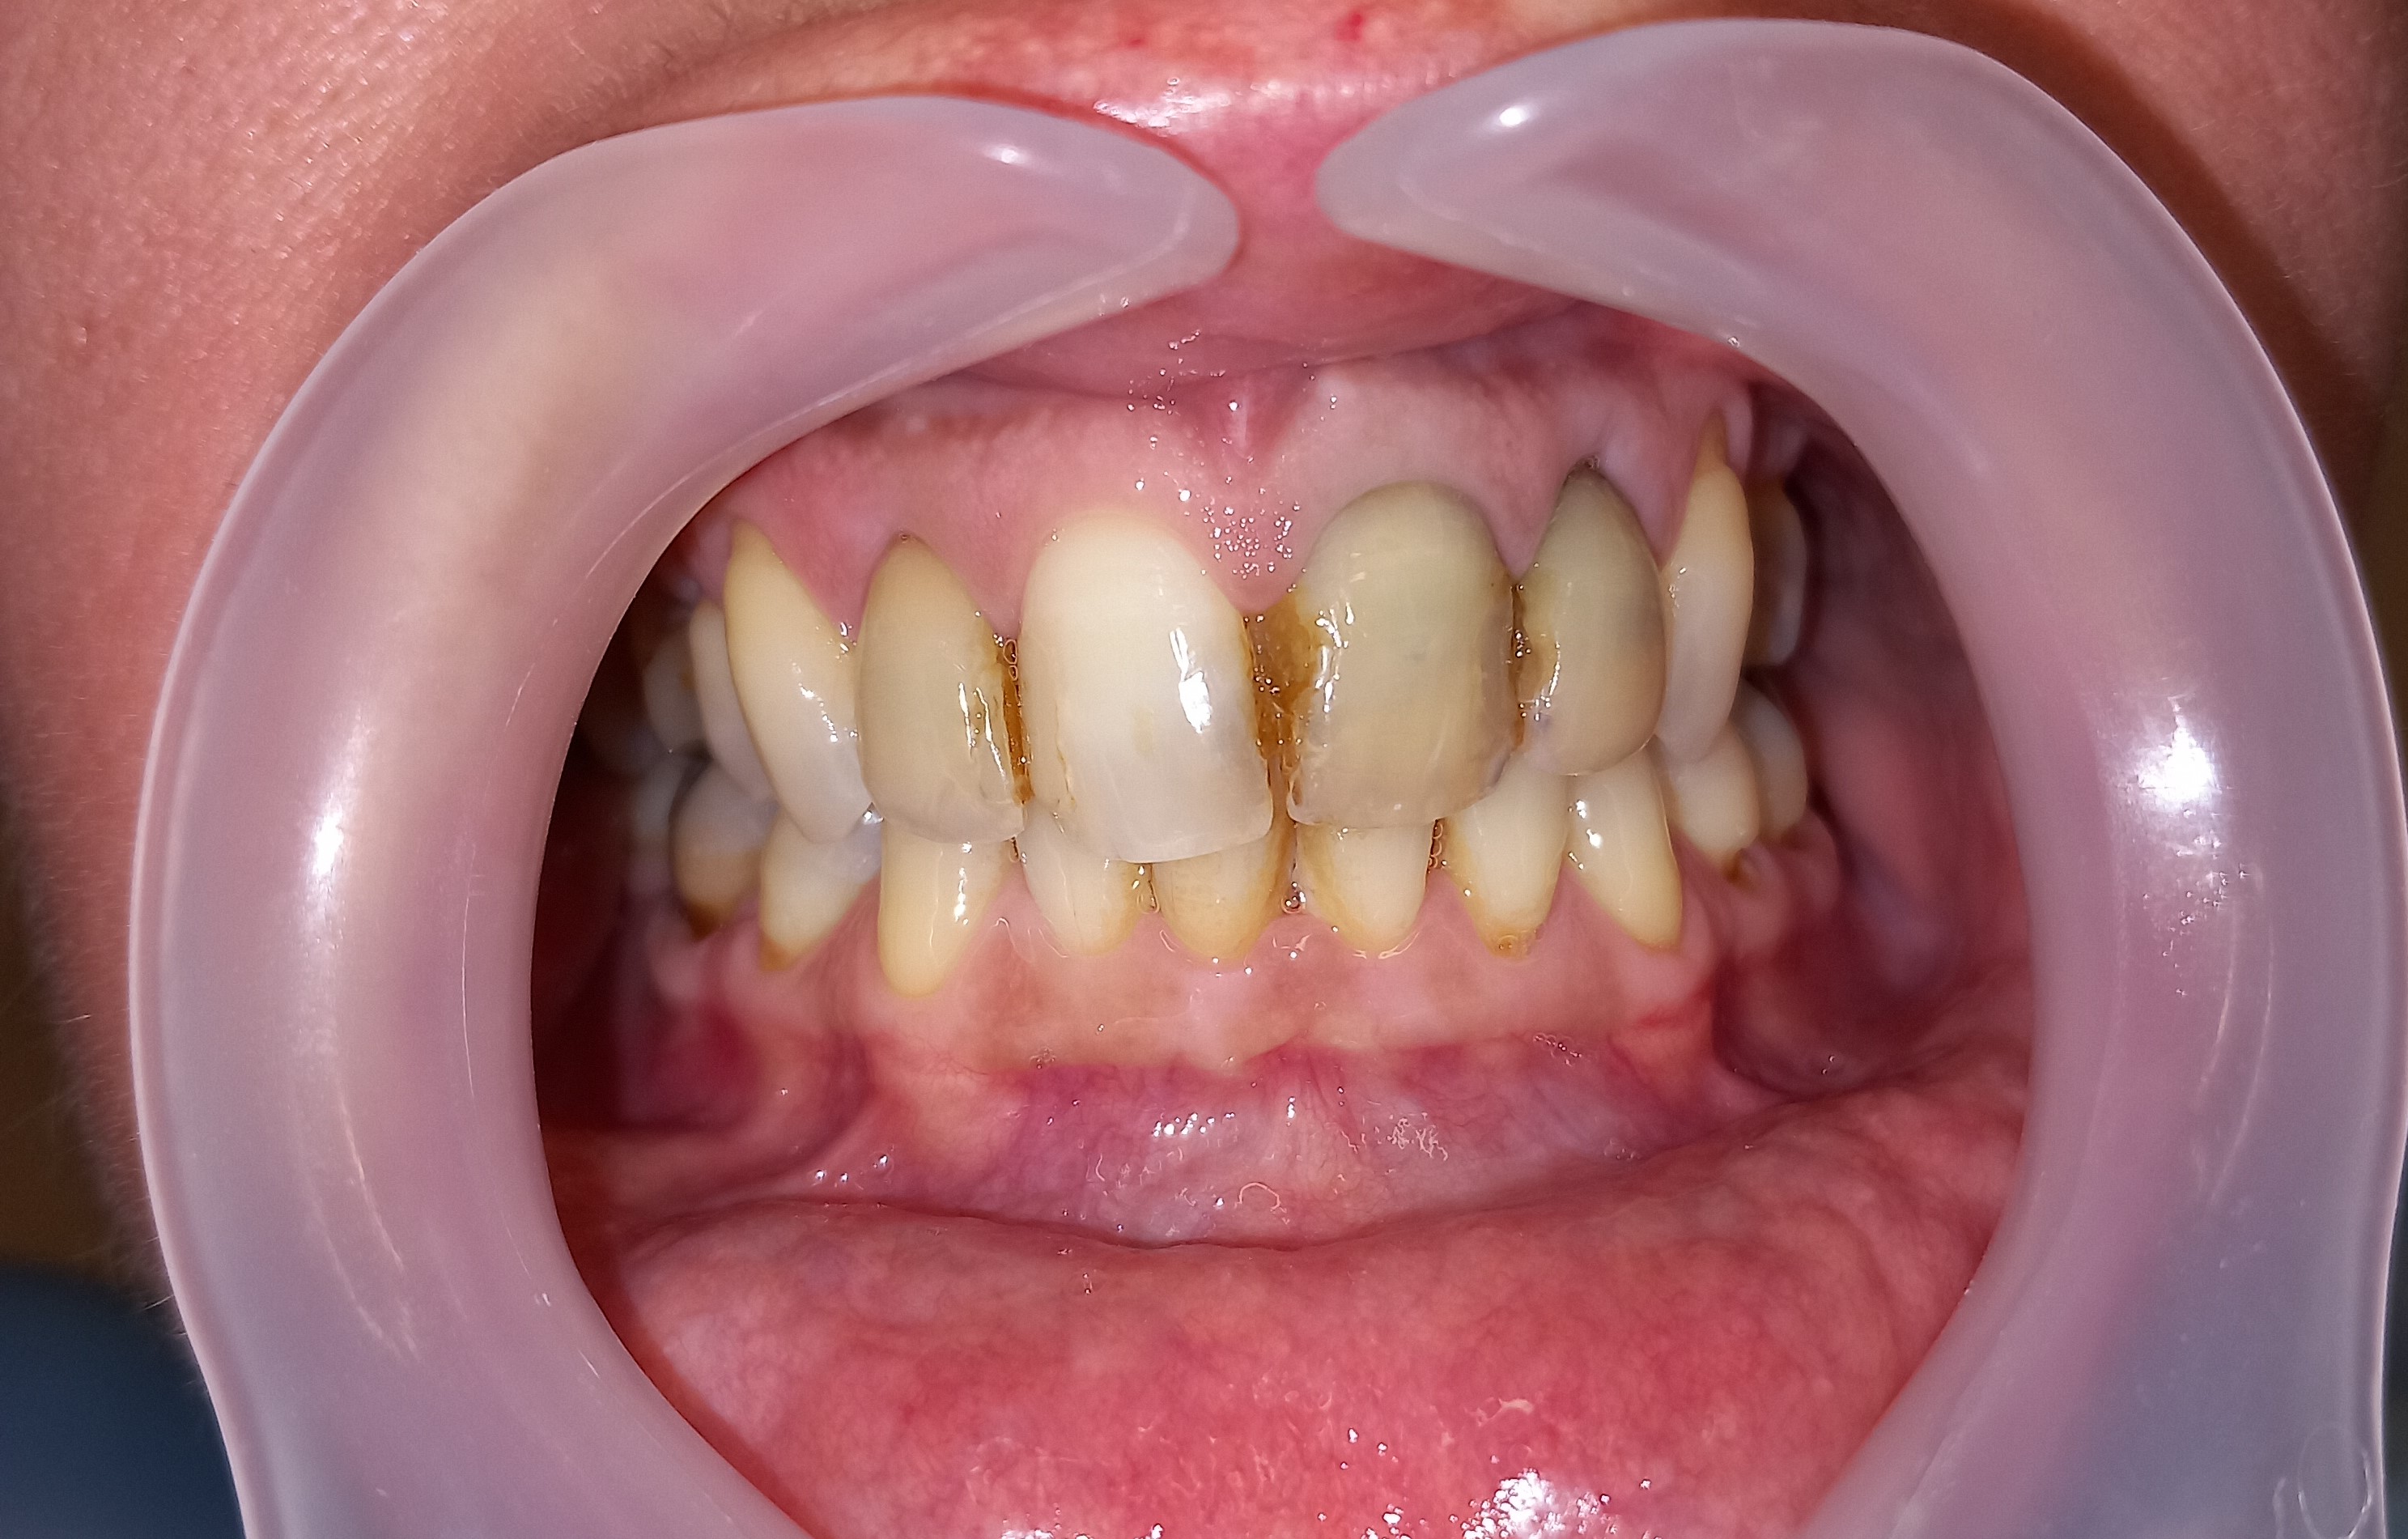

Ο ασθενής δεν είναι ευχαριστημένος με την αισθητική των 6 άνω πρόσθιων δοντιών. Επιπρόσθετα αυτά τα δόντια είχαν παλιές μεγάλες ανασυστάσεις, οι οποίες είχαν επανατερηδονιστεί. Για όλους τους ανωτέρους λόγους αποφασίστηκε, μετά από την απαραίτητη συζήτηση με τον ασθενή η αποκατάσταση των δοντιών με ολοκεραμικές θήκες. Τα δόντια τροχίστηκαν, αντικαταστάθηκαν οι παλιές εμφράξεις των δοντιών και στη συνέχεια λήφθηκαν αποτυπώματα, τα οποία στάλθηκαν στον οδοντοτεχνίτη. Σε όλη τη διάρκεια, που ο οδοντοτεχνίτης κατασκεύαζε τις νέες προσθετικές αποκαταστάσεις ο ασθενής φορούσε προσωρινές θήκες, οι οποίες είχαν ικανοποιητική αισθητική εμφάνιση.

Είναι σημαντικό να τονιστεί οτι ο ασθενής επιθυμούσε οι θήκες των 6 άνω πρόσθιων δοντιών να είναι αισθητά λευκές, παρόλο που διέφεραν χρωματικά από τα υπόλοιπα δόντια.

Αρχική κλινική εικόνα των 6 άνω πρόσθιων δοντιών